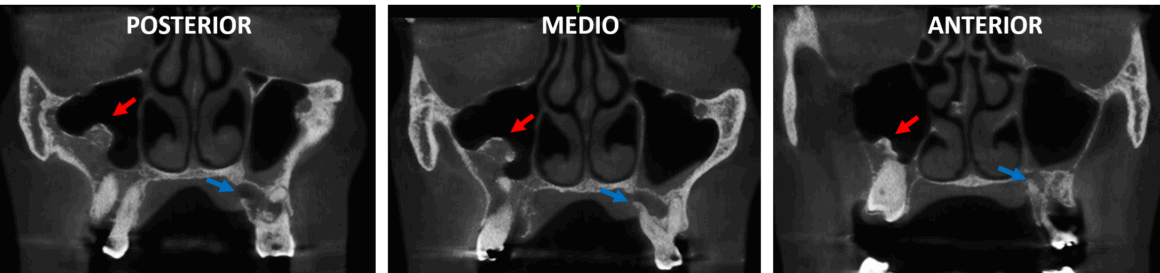

Fig.1

En la evaluación con tomografía computarizada cone beam, se realizó la reconstrucción panorámica del maxilar superior (Fig.1), donde se observa completo ambos senos maxilares, evidenciando en el antro derecho una imagen hiperdensa que ocupa parcialmente dicha cavidad aérea (flecha roja). Nótese la impactación dentaria de los caninos.